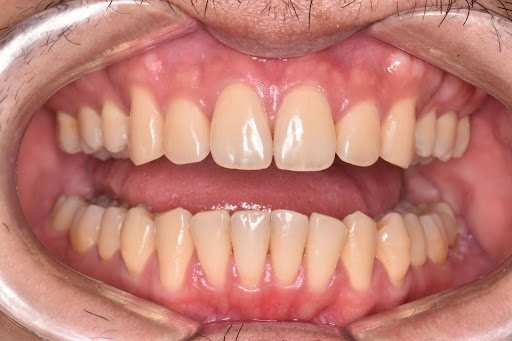

次にこちらの写真はワイヤー矯正の症例写真です。

術前の写真です。

術後の写真となっております。